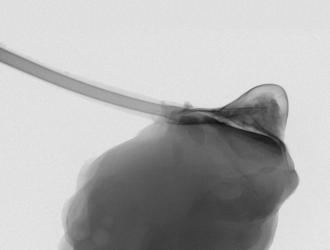

Arriva “Therepi”, un microscopico serbatoio di farmaci che si attacca direttamente al cuore e che può essere riempito dall'esterno in modo semplice grazie a un “tubicino” di collegamento che finisce sotto cute.

Therepi rilascia farmaci in modo controllato e localizzato per...